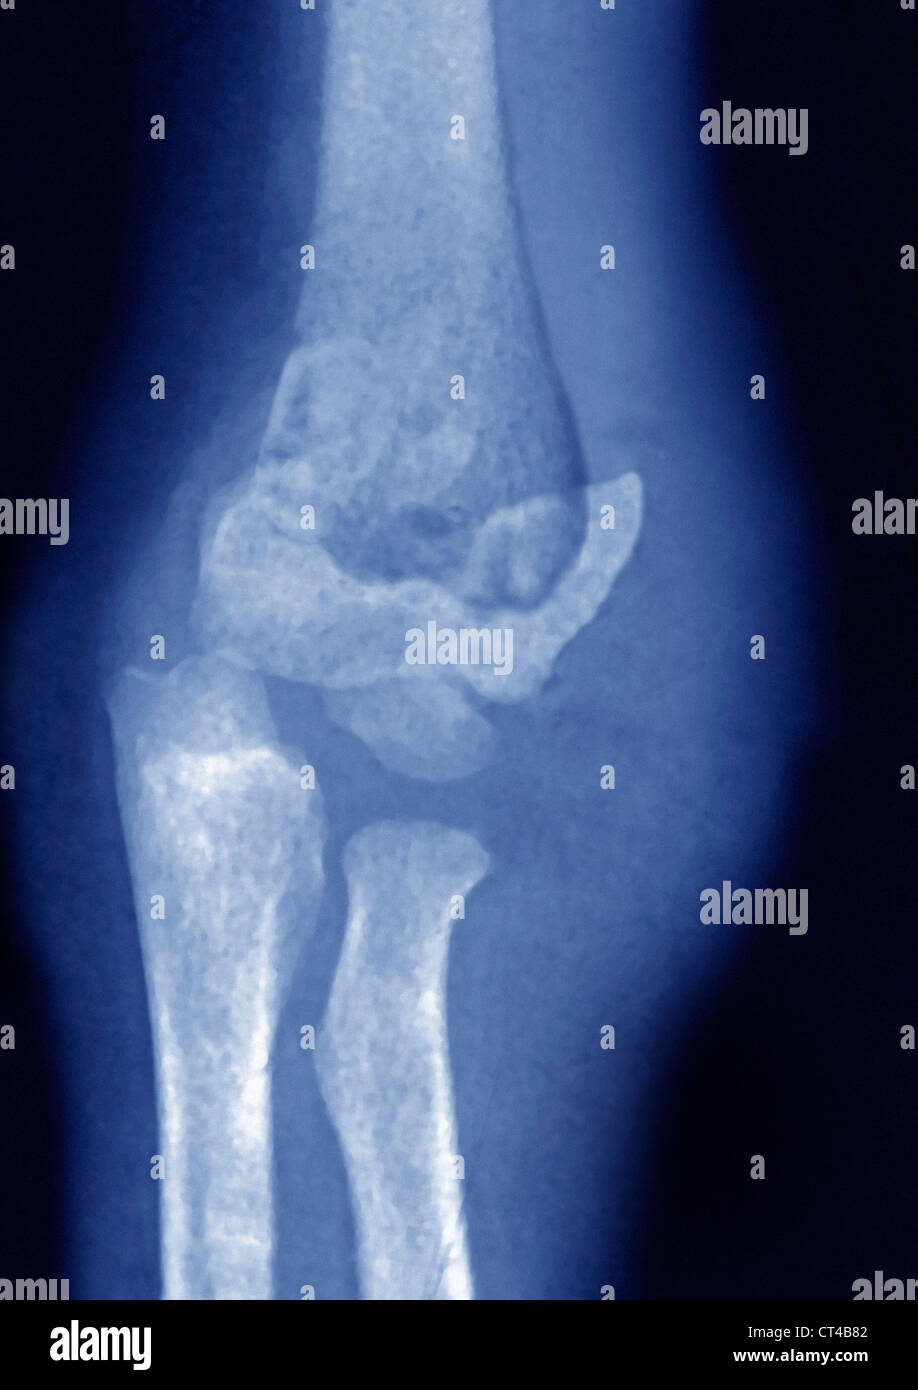

From www.animalia-life.club

Elbow X Ray Fracture Can You Bend Fractured Elbow Other signs and symptoms of a fracture. You may hear or feel a pop or crack in. learn information about broken elbow symptoms and signs such as swelling, severe pain, discoloration, deformity,. elbow fractures can result from a fall, a direct blow to the elbow, or an abnormal twisting of the arm. pain, bruising, and swelling around. Can You Bend Fractured Elbow.